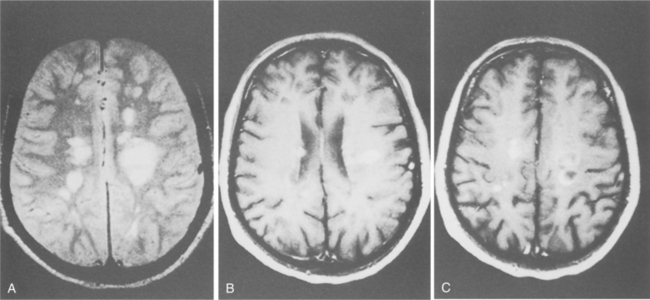

Fig. 31-8 shows the plaques seen on MRI. The lesions do not always correlate with the clinical signs, and there can be evidence of focal lesions in the absence of disease. In fact, the vast majority of enhancing lesions are considered to be asymptomatic when they first appear on the brain scan. However, there is a correlation between periods of clinical worsening of the disease and increases in the total number of lesions, the number of new lesions, and the total area of enhancement on MRI.23 Thus, a single brain MRI scan after a first event is highly prognostic of development of clinically definite MS.137 Fig. 31-9 shows an example of aggressive MS over 2 years revealed in MRI imaging.

Figure 31-8 A, Typical scattered, variably sized plaques in the brain associated with the diagnosis of multiple sclerosis (MS). B, Contrast-enhanced magnetic resonance imaging reveals scattered area of solid and ring-shaped enhancement. C, Note the atrophy, greater than would be expected for the person’s age, a common finding in MS. (From Ramsey R: Neuroradiology, Philadelphia, 1994, Saunders.)